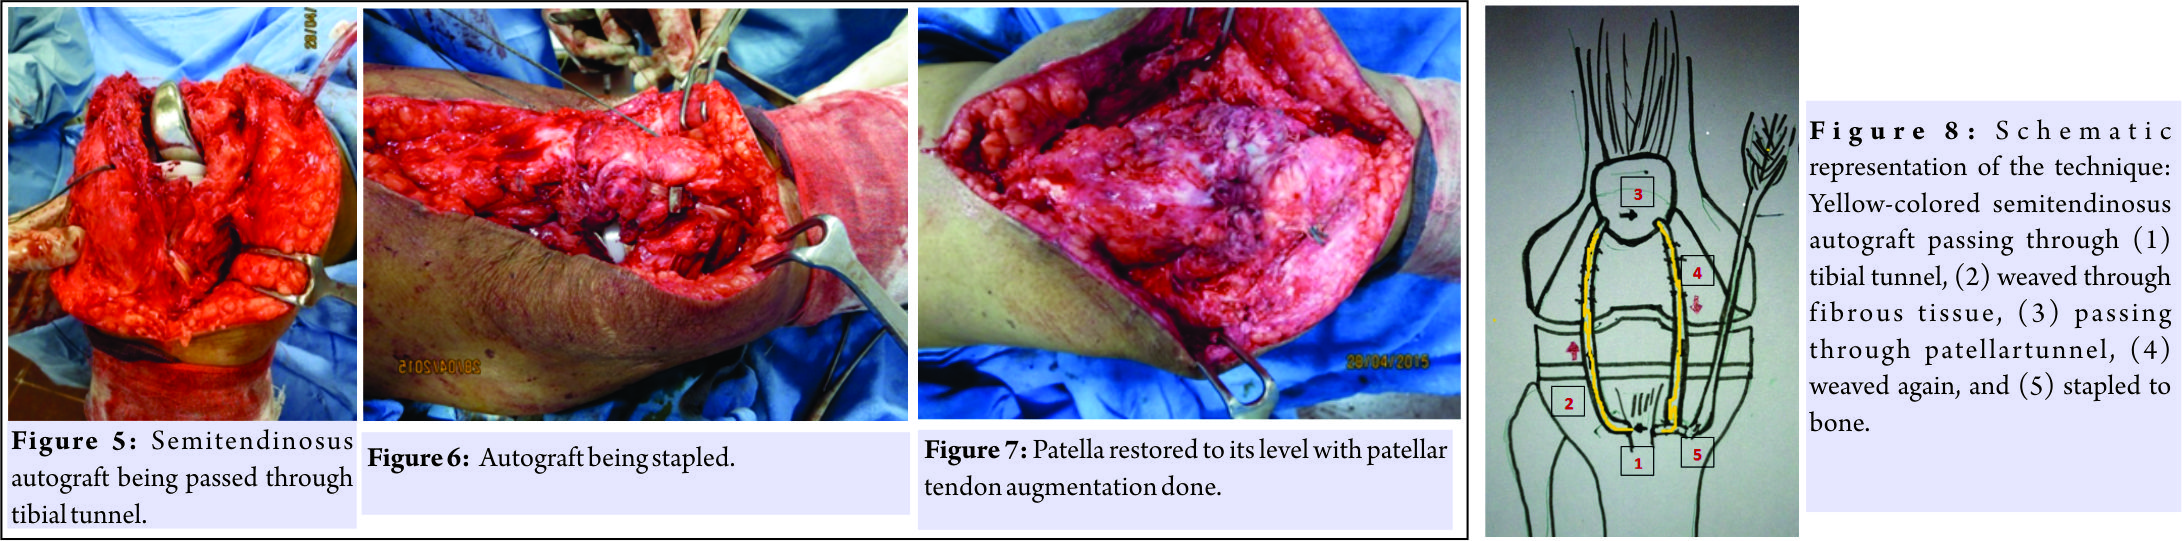

A 69-year-old woman underwent bilateral total knee replacement for symptomatic Grade III osteoarthritis of both the knees. The surgery was performed using a midline skin incision and midvastus approach. A cemented cruciate substituting posterior stabilized implant(Stryker NRG Scorpio, right knee femoral component size 4, tibial component size 4,and insert thickness 8 mm and left knee femoral component of size 5, tibial component size 4, and insert thickness 10 mm) was used. The patella was everted during surgery as usual and patelloplasty was done. She recovered well in the post-operative period,attaining range of motion from 0 to 90° by the end of 1st week of surgery, and could walk comfortably without support 4 weeks after the surgery.She did not report until about 6 months after surgery when she started having difficulty in walking with right knee and in getting up from sitting position.She did not have any pain and did not report any trauma. On examination, she had an extension lag of 30° and could flex up to 110° (Fig. 1). The knee was not warm orerythematous, but patella was located higher than normal. There was minimal tenderness around patellar tendon and tibial tuberosity, and x-ray revealed patella alta on the right side which led to the diagnosis of patellar tendon avulsion (Fig. 2, 3, 4). On exploration, patellar tendon was found to be avulsed from tibial tuberosity with 8–10 cm proximal migration of patella and extensive fibrosis in between (Fig. 1). After debridement, the patella was mobilized down to its normal position only with aquadriceps snip.The semitendinosus tendon was harvested through a small incision over the pes anserinus using tendon stripper, keeping its tibial attachment intact. One 6 mm wide tunnel was drilled horizontally into the tibial tuberosity and one transversely in the upper half of the patella. The free end of the harvested tendon was first made to pass through the tibial tunnel from medial to lateral direction and was then weaved through the patellar tendon remnant and fibrous tissue in a proximal direction toward patella. It was then made to pass through the patellar tunnel from lateral to medial end and was again weaved through the available scar tissue and carried distally to end just medial to the tibial tuberosity where it was stapled after tensioning at 30° of knee flexion (Fig. 5, 6, 7, 8).

The knee was not warm orerythematous, but patella was located higher than normal. There was minimal tenderness around patellar tendon and tibial tuberosity, and x-ray revealed patella alta on the right side which led to the diagnosis of patellar tendon avulsion (Fig. 2, 3, 4). On exploration, patellar tendon was found to be avulsed from tibial tuberosity with 8–10 cm proximal migration of patella and extensive fibrosis in between (Fig. 1). After debridement, the patella was mobilized down to its normal position only with aquadriceps snip.The semitendinosus tendon was harvested through a small incision over the pes anserinus using tendon stripper, keeping its tibial attachment intact. One 6 mm wide tunnel was drilled horizontally into the tibial tuberosity and one transversely in the upper half of the patella. The free end of the harvested tendon was first made to pass through the tibial tunnel from medial to lateral direction and was then weaved through the patellar tendon remnant and fibrous tissue in a proximal direction toward patella. It was then made to pass through the patellar tunnel from lateral to medial end and was again weaved through the available scar tissue and carried distally to end just medial to the tibial tuberosity where it was stapled after tensioning at 30° of knee flexion (Fig. 5, 6, 7, 8). We used non-absorbable sutures to secure and reinforce these mitendinosus tendon passing over the patellar tendon. An intraoperative flexion of 90 could be attained easily, without tension. Post-operative radiographs showed good restoration of the patellar height with a Caton–Deschamps index of 1 (Fig. 9,10,11). The patient was given a cylinder cast for 4 weeks and allowed full weight bearing. Atthe last follow-up of 2 years after the surgery, the range of motion was 0–110° with no extension lag and the patient was ambulatory without any support.

We used non-absorbable sutures to secure and reinforce these mitendinosus tendon passing over the patellar tendon. An intraoperative flexion of 90 could be attained easily, without tension. Post-operative radiographs showed good restoration of the patellar height with a Caton–Deschamps index of 1 (Fig. 9,10,11). The patient was given a cylinder cast for 4 weeks and allowed full weight bearing. Atthe last follow-up of 2 years after the surgery, the range of motion was 0–110° with no extension lag and the patient was ambulatory without any support.

Repair of a chronically torn patellar tendon in TKA provides a good outcome, if following points are taken care of:(1) Patellar position should be well restored, (2) the tibial insertion of the semitendinosus graft should be kept intact which gives additional strength to the repair, (3) the autograft should be weaved into the residual tissue (patellar tendon fat pad)for extra strength and smooth mobility, (4) tunnels should be made both in both the patella and the tibial tuberosity, and (5) adequate tensioning should be done before final fixation with a staple.